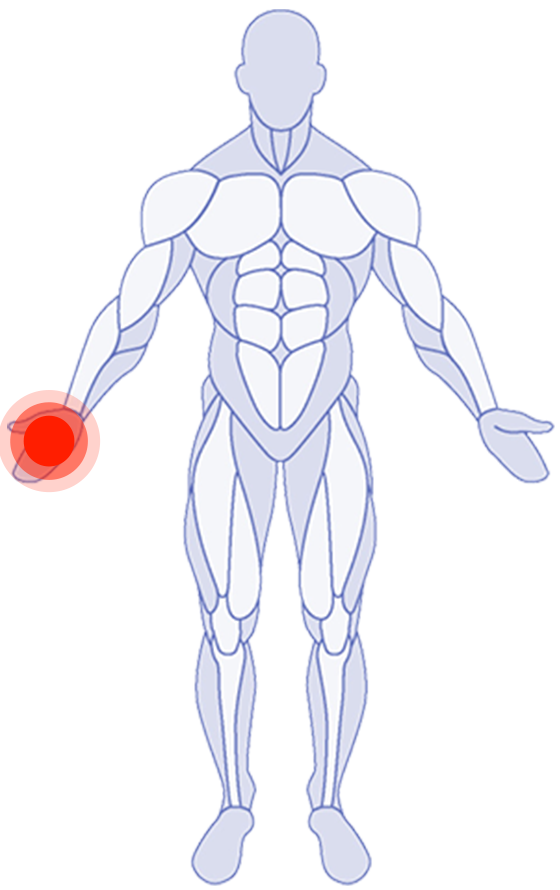

Where do you need attention?